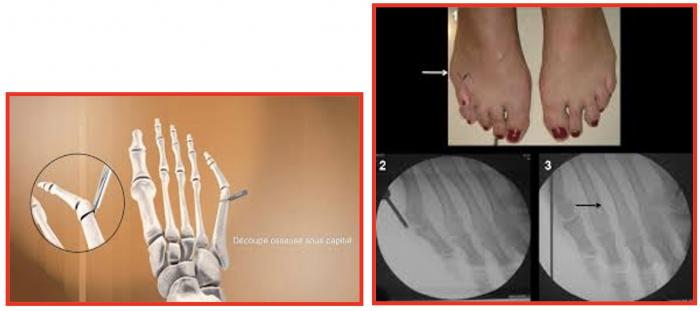

Chirurgical :

Les techniques « conventionnelles (ciel ouvert) » permettant, sous contrôle de la vue de corriger la déformation.

Au contraire, les techniques « percutanées » utilisent plusieurs incisions millimétriques, permettant le passage d’instruments spécifiques qui sont guidés sous la peau par un contrôle radiographique.

Au contraire, les techniques « percutanées » utilisent plusieurs incisions millimétriques, permettant le passage d’instruments spécifiques qui sont guides sous la peau par un contrôle radiographique.